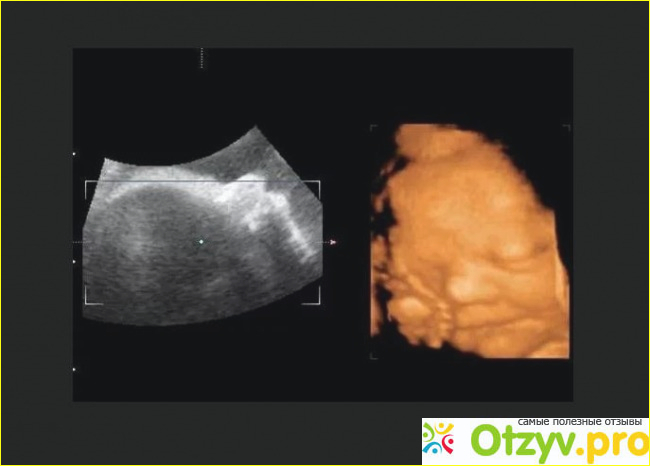

Узи при беременности - это процедура номер один. Каждая женщина проходит очень много процедур узи пока вынашивает ребенка. Делать эту процедуру очень важно, так можно отслеживать все изменения, происходящие с ребенком, и хорошие, и негативные. Для спокойствия будущей мамочки проходить плановые узи очень важно, ведь когда ты знаешь, что с ребенком все в порядке и развивается он хорошо, то ты не переживаешь за это.